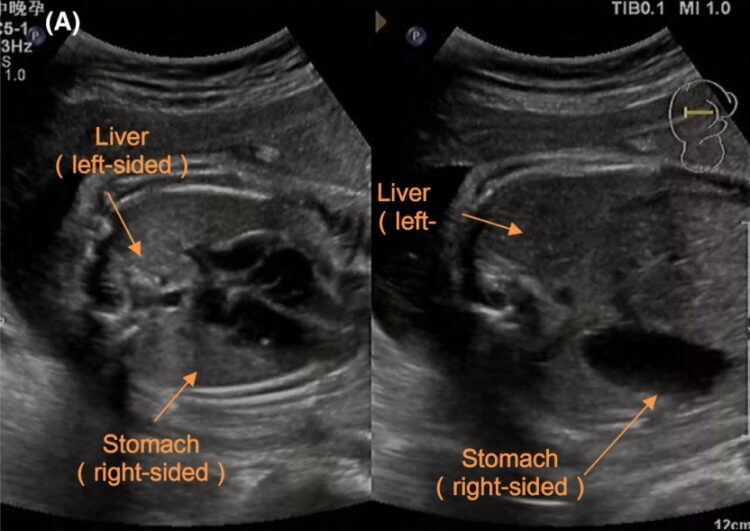

사례를 보고한 중국 의료진은 20대 여성 환자가 임신 초기에 내원해 정기 산전 검진을 받았다고 밝혔다. 임신 27주 6일째 태아 심장 초음파 검사에서 좌우 대칭 우심증(심장이 정상 위치가 아닌 오른쪽에 있는 상태)이 처음 관찰됐다. 이후 추가적으로 시행한 검사에서 주요 혈관, 장기들이 정상 위치에서 좌우 대칭에 해당하는 반대쪽에서 발견되면서 태아의 전신내장역위증이 확정됐다.

전신내장역위증이 있어도 대부분 완전한 정상 생활이 가능하다. 평생 모르고 살다가 군 검사나 건강검진에서 처음 발견하는 경우가 많은 것도 이 때문이다. 의료진은 "태아의 자세, 임신 주수, 검사자의 숙련도에 따라 전신내장역위증의 산전 진단이 어려울 수 있다"고 했다.